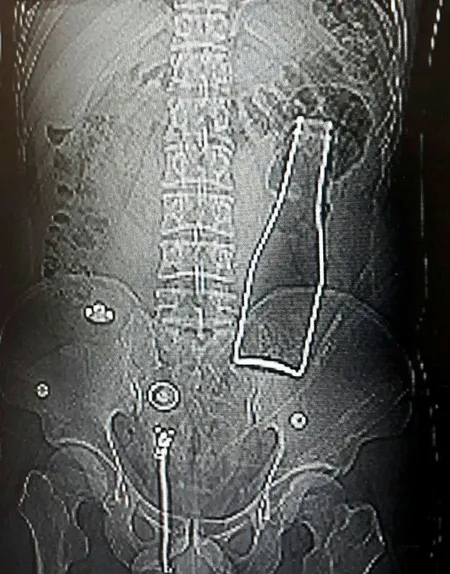

Karaman Eğitim ve Araştırma Hastanesi'ne, 28 Haziran Pazar gecesi gelen A.E., karın ağrısı şikayeti olduğunu söyledi. Bunun üzerine röntgen filmi çekilen gencin kalın bağırsağında şişe olduğu görüldü. Makattan girdiği belirlenen şişe, yaklaşık 1 saat süren ameliyatla çıkarıldı.